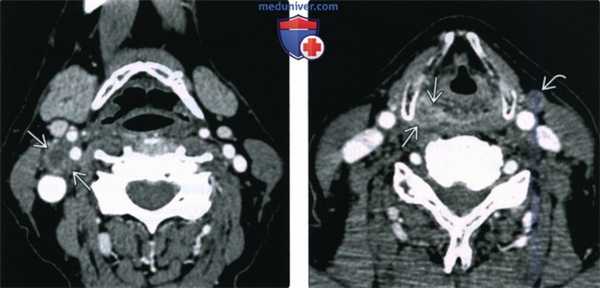

(Слева) Т1ВИ C+FS, аксиальная проекция: крупный конгломерат вторично измененных лимфоузлов. Определяются признаки эксгракапсулярного распространения опухоли и наличие новообразования в левом грушевидном синусе (низкодифференцированный ПКР, T2N2c). После химиолучевой терапии и удаления лимфоузлов с остаточной опухолью прошло четыре года, признаки рецидива не выявлены.

(Справа) При аксиальной КТ с КУ у пациента с жалобами на нарушение глотания и боль в ухе визуализируется образование, умеренно накапливающее контраст, вовлекающее все стенки грушевидного синуса, распространяющееся в окружающую клетчатку. Опухоль распространяется кзади в превертебральные мышцы в, заглоточная жировая клетчатка не визуализируется.